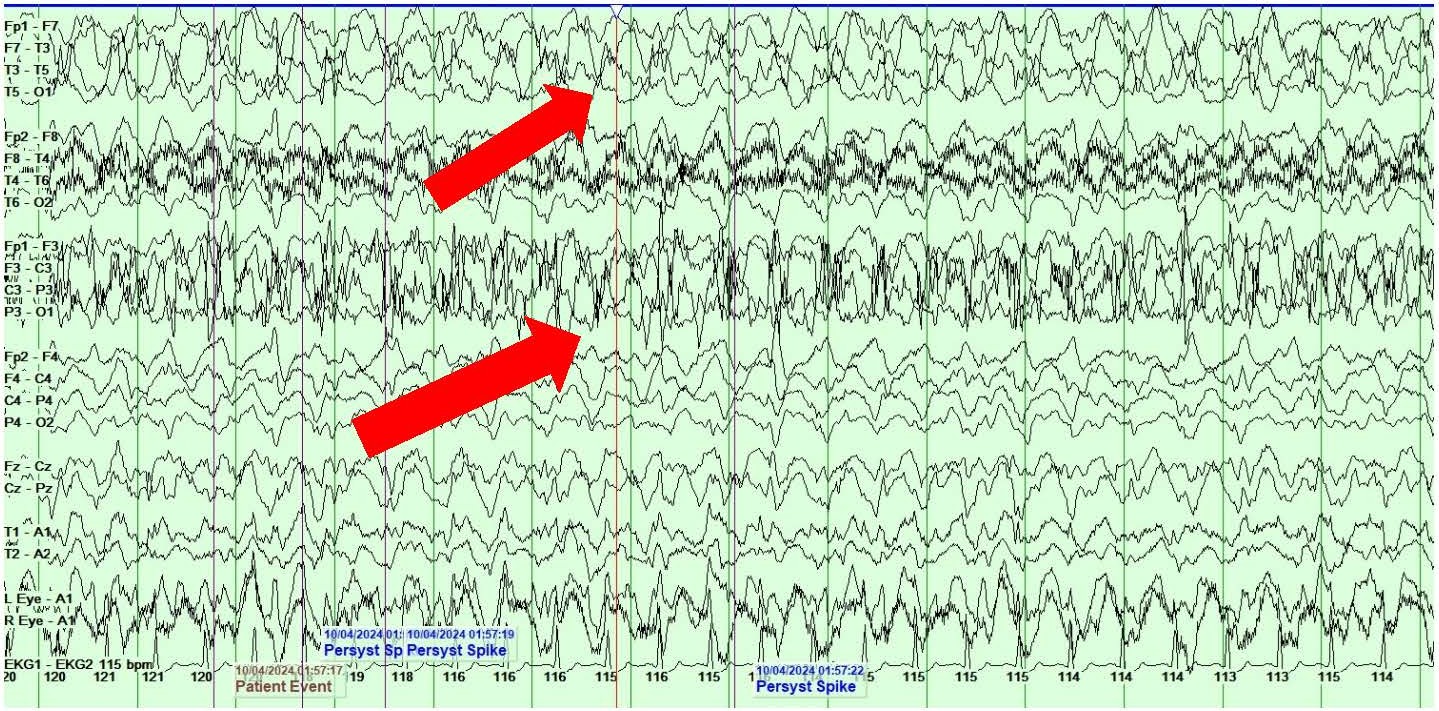

She also showed the presence of right hemispheric LPDs at 1-2 Hz and LRDA at 2-3 Hz that lasted for 1-10 minutes and occurred consistently with stimulation during physical manipulation or care by the medical providers and nursing staff (Figures 4A and 4B). These findings occurred independent of the previously described left hemispheric onset seizures mentioned above. They were felt to represent SIRPIDs (SI-LPDs and SI-LRDA).

Figures 4. A, B) Screenshots from Video EEG showing RIGHT hemispheric SIRPIDs provoked by stimulation (SI-LRDA and SI-LPDs) (marked by red arrows).